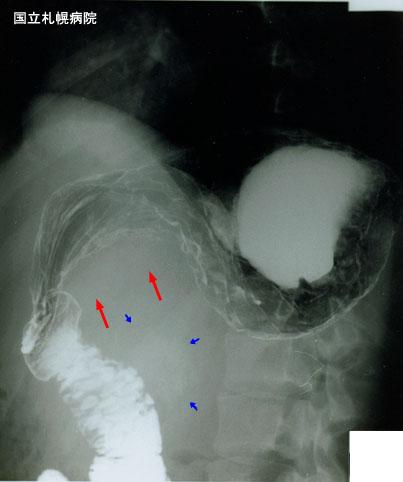

疾病(病理主体)的分类恶性非上皮性肿瘤/其他

检查方法X线

肿瘤最大直径40以上